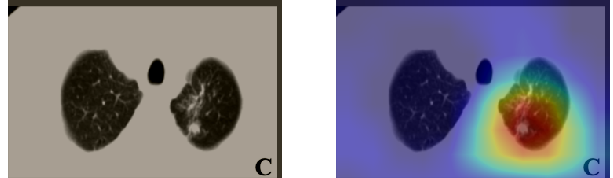

Figure 16 shows various CT scans where only one lung is visible. The CT scans are also extracted from the paper [58] and show different CT manifestations of COVID-19 pneumonia marked by red squares. The InceptionV3 model is capable to classify them correctly as COVID-19, although it is trained on CT scans where the entire lung is visible. Intriguingly, when applying Grad-CAM we can see that all regions of abnormalities are accurately localized. This also proves the potential of our model to detect COVID-19 abnormalities in CT images outside the dataset used for training.